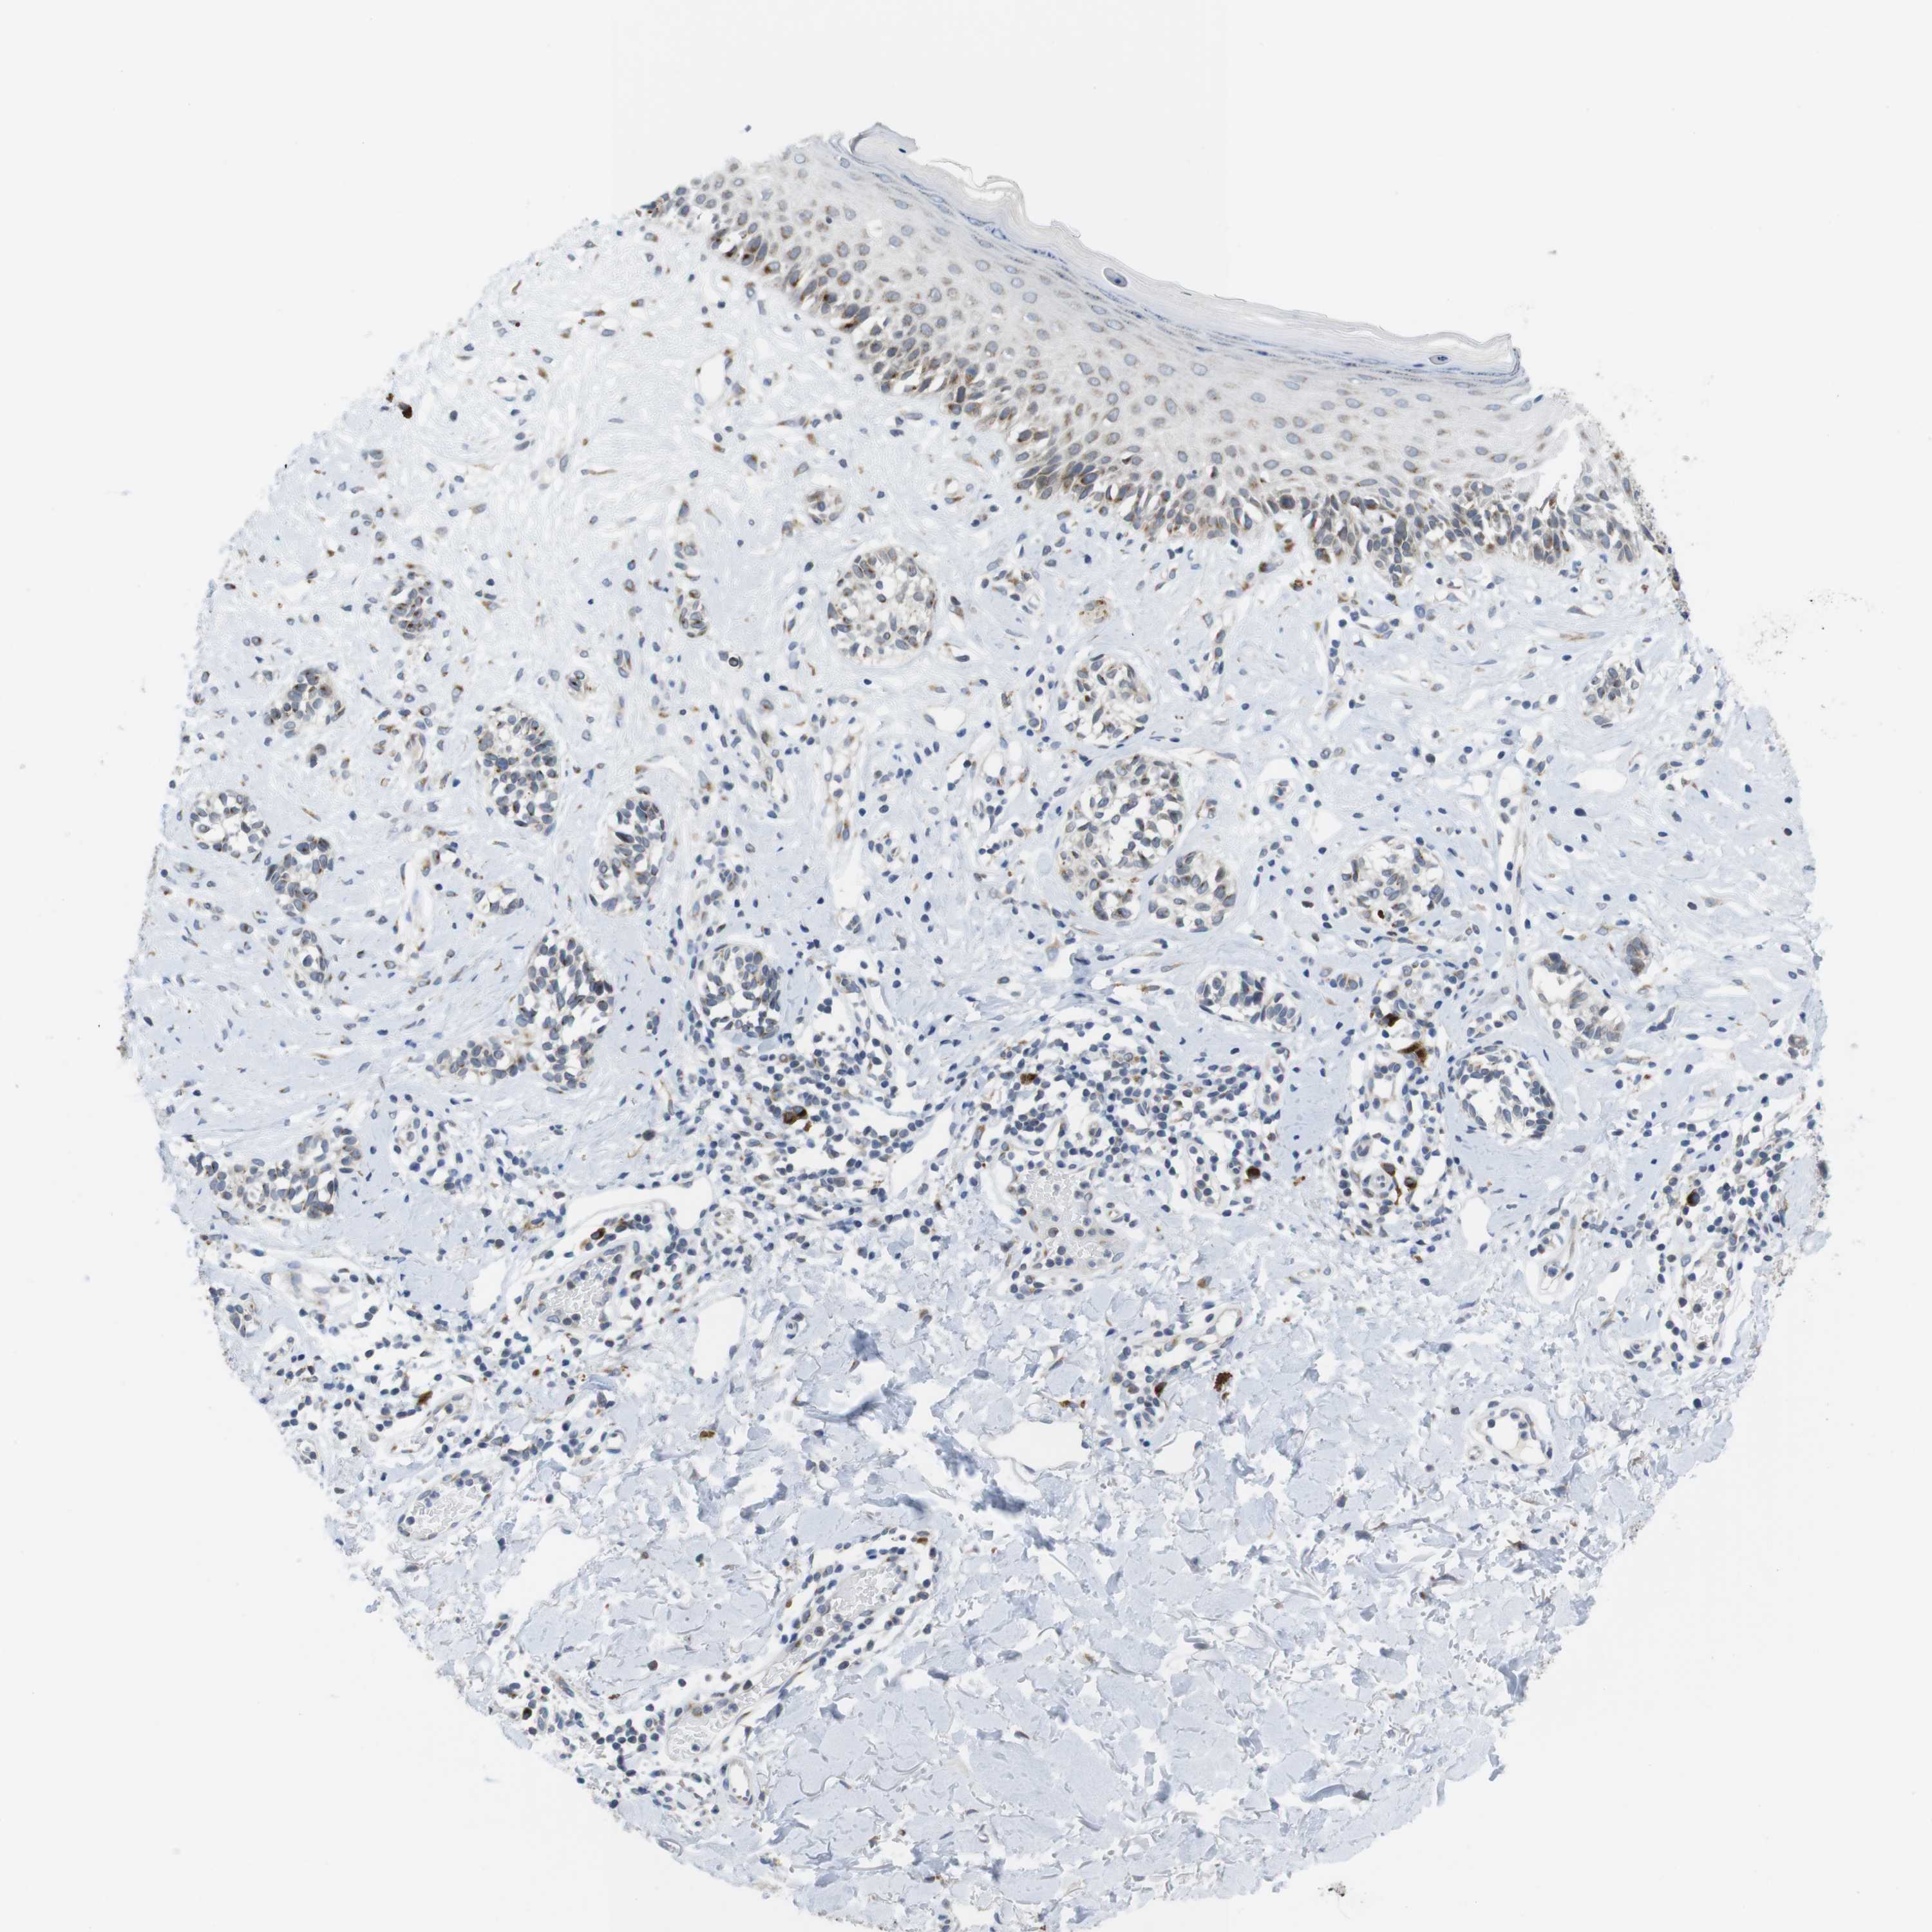

MELANOMA - Protein expressioni

A mouse-over function shows sample information and annotation data. Click on an image to view it in a full screen mode. Samples can be filtered based on level of antibody staining by selecting one or several of the following categories: high, medium, low and not detected. The assay and annotation is described here.

Note that samples used for immunohistochemistry by the Human Protein Atlas do not correspond to samples in the TCGA dataset.

Antibody stainingi

Antibody staining in the annotated cell types in the current human tissue is reported as not detected, low, medium, or high, based on conventional immunohistochemistry profiling in selected tissues. This score is based on the combination of the staining intensity and fraction of stained cells.

Each image is clickable and will lead to virtual microscopy that enables deeper exploration of all samples and also displays staining intensity scores, fraction scores and subcellular localization as well as patient and tissue information for each sample.

Antibody HPA015242

Antibody HPA015968

Staining

High

Medium

Low

Not detected

Intensity

Strong

Moderate

Weak

Negative

Quantity

>75%

75%-25%

<25%

None

Location

Nuclear

Cytoplasmic/membranous

Cytoplasmic/membranous,nuclear

Malignant melanoma, NOS

Malignant melanoma, Metastatic site